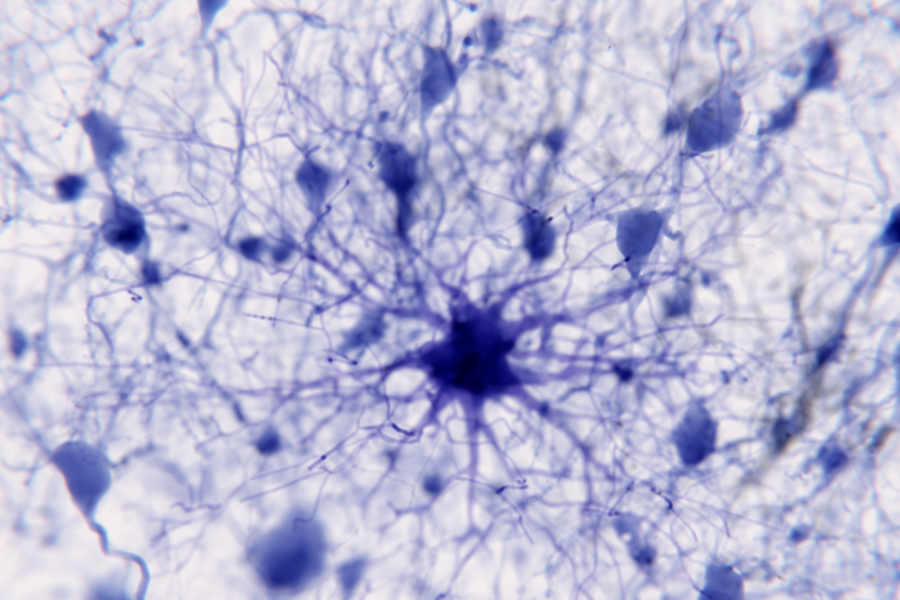

The Glial Neurobiology, Cognition and Behaviour Research Group aims to learn how glial cells contribute to brain circuit function. Most brain cells are glia – they far exceed neurons in number and diversity. They can be divided into five major types: neural stem cells; astrocytes; oligodendrocytes; oligodendrocyte progenitor cells (OPCs) and microglia.

The Reserach Group is particularly interested in discovering how oligodendrocytes allow brain circuits to adapt with life experience and how this impacts behaviour. Oligodendrocytes produce a fatty insulating substance – called myelin – that they wrap around the long thin processes (axons) of electrically active neurons. This insulation allows axons to carry electrical impulses rapidly and reliably from one part of the brain to another. The addition of new myelin and the restructuring of existing myelin can fine-tune the speed of information transfer, and we are seeking to understand how these changes occur, and how this kind of plasticity helps us to think, feel and behave.